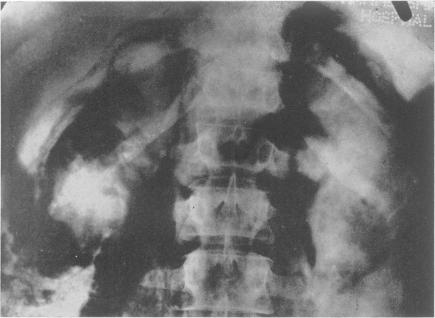

Radiology in the investigation and management of hypertension.

Postgrad Med J. 1958 Oct;34(396):514-23 passim. doi: 10.1136/pgmj.34.396.514.